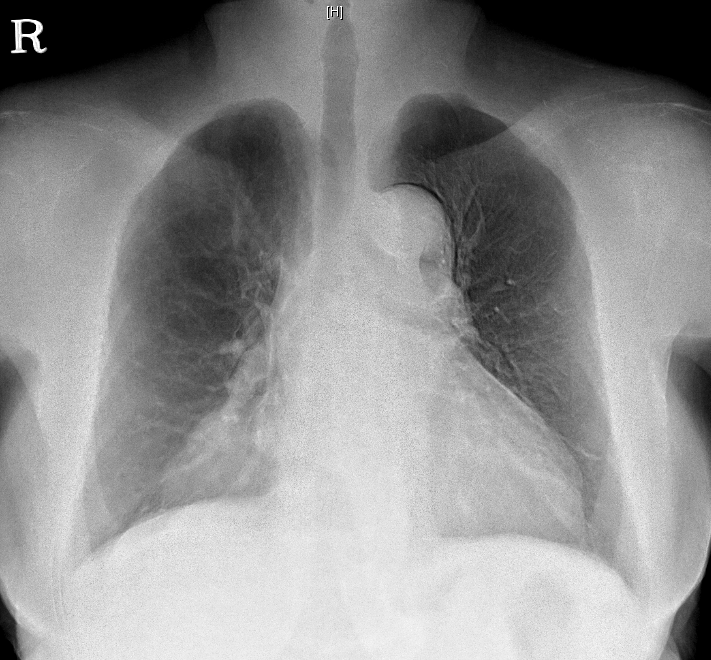

DM, HTN °ú°Å·Â ÀÖ´Â ºÐÀ¸·Î hip osteoarthritis ·Î THR ½ÃÇà ¿¹Á¤ÇÏ´ø Áß preop CXR abnormality ·Î ÀÇ·ÚµÊ.

<³»¿ø½Ã CXR>

<3³âÀü CXR>